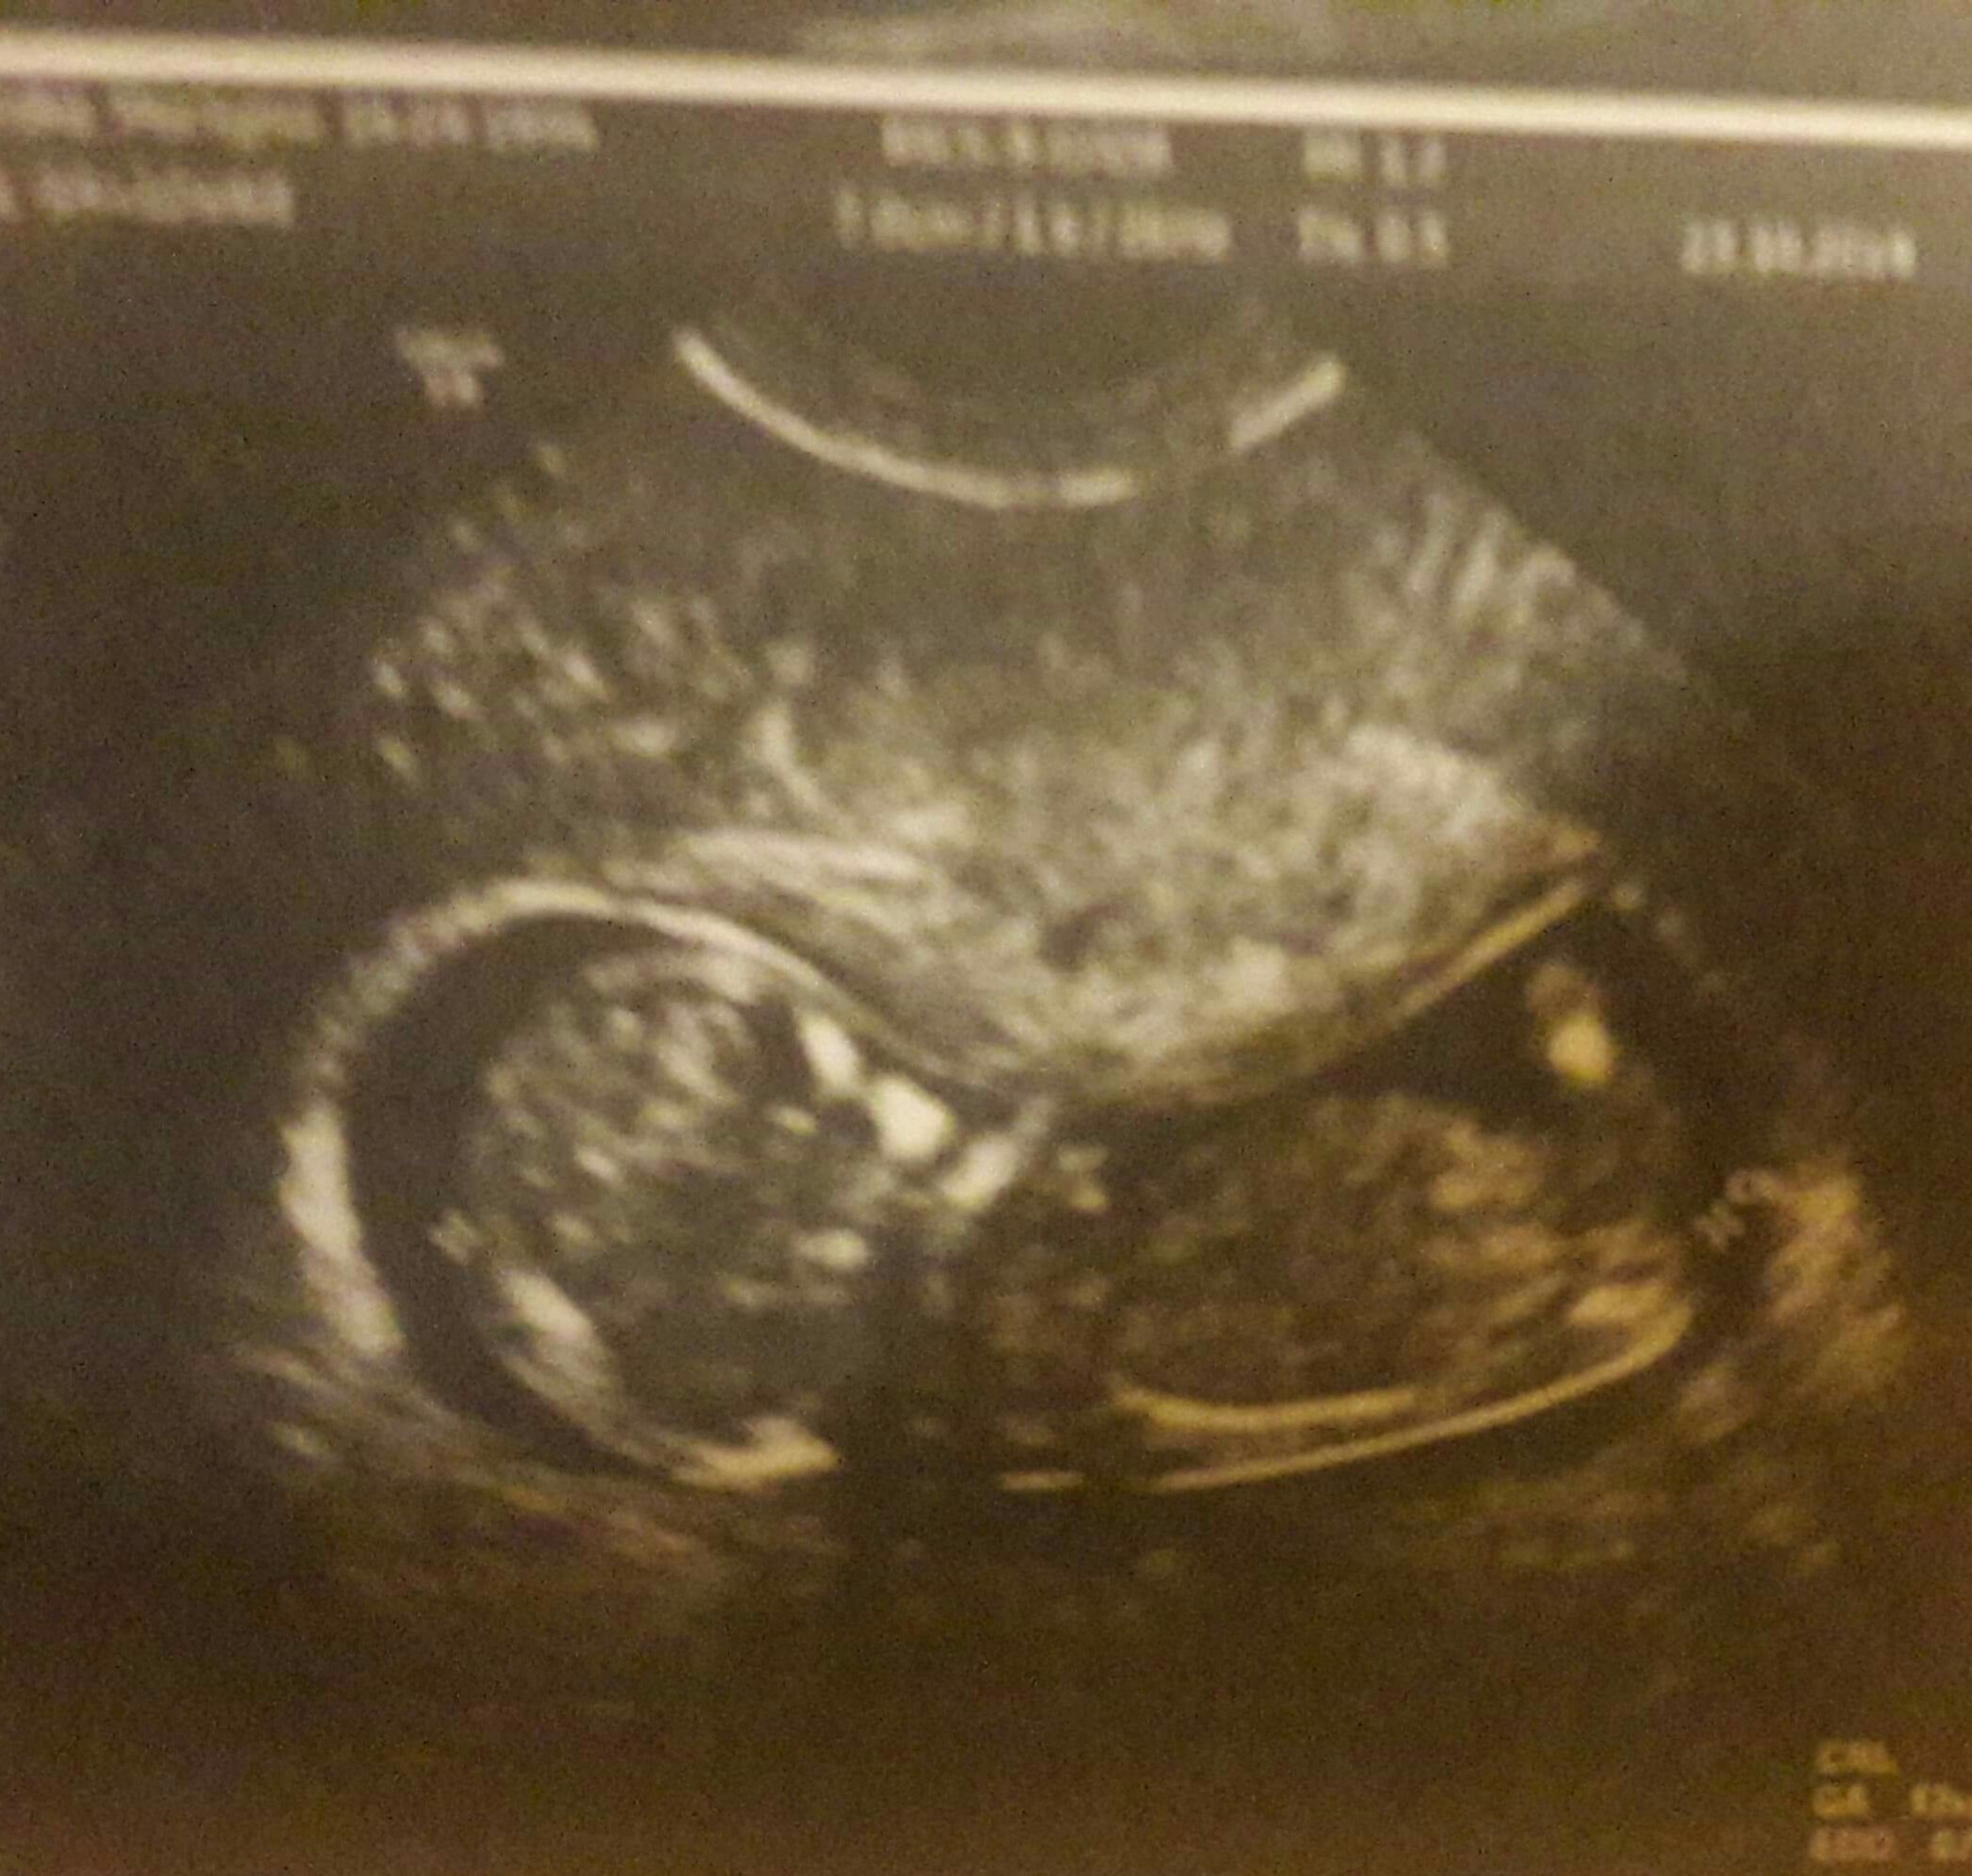

Witam w 19 tygodniu ciąży dowiedziałam się ze będę miała dziewczynkę w 20 tyg okazało się jednak , że to chłopak. Sama już nie wiem bo na jednym usg widać na pewno dziewuche a na drugim chłopca. Może to pempowina ?? Może ktoś mi pomoże rozwiązać ta zagadkę

no nic , zobaczymy na kolejnym USG. To doswiadczona Pani wiec chyba wie co mówi a ja ogladam zdjęcia pod każdym kątem i szukam śladów kobiecych